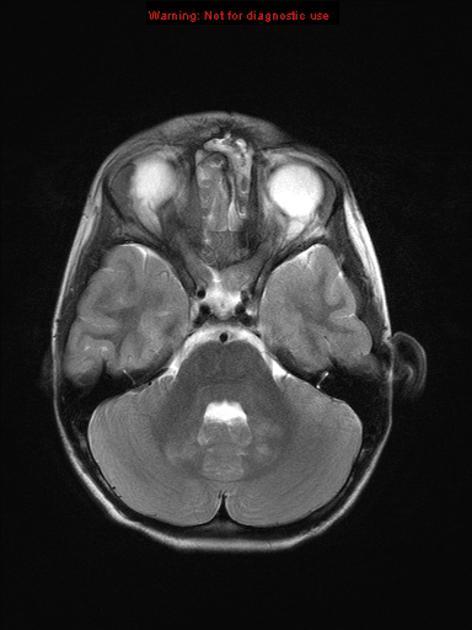

基本病史:6 岁女孩,既往体健,近期左眼视力明显下降,行颅脑 MRI 检查结果如下。

图 1 MRI 检查轴位 T2WI 序列显示鞍区及鞍上区见长 T2 异常信号实性肿块,沿视神经走行